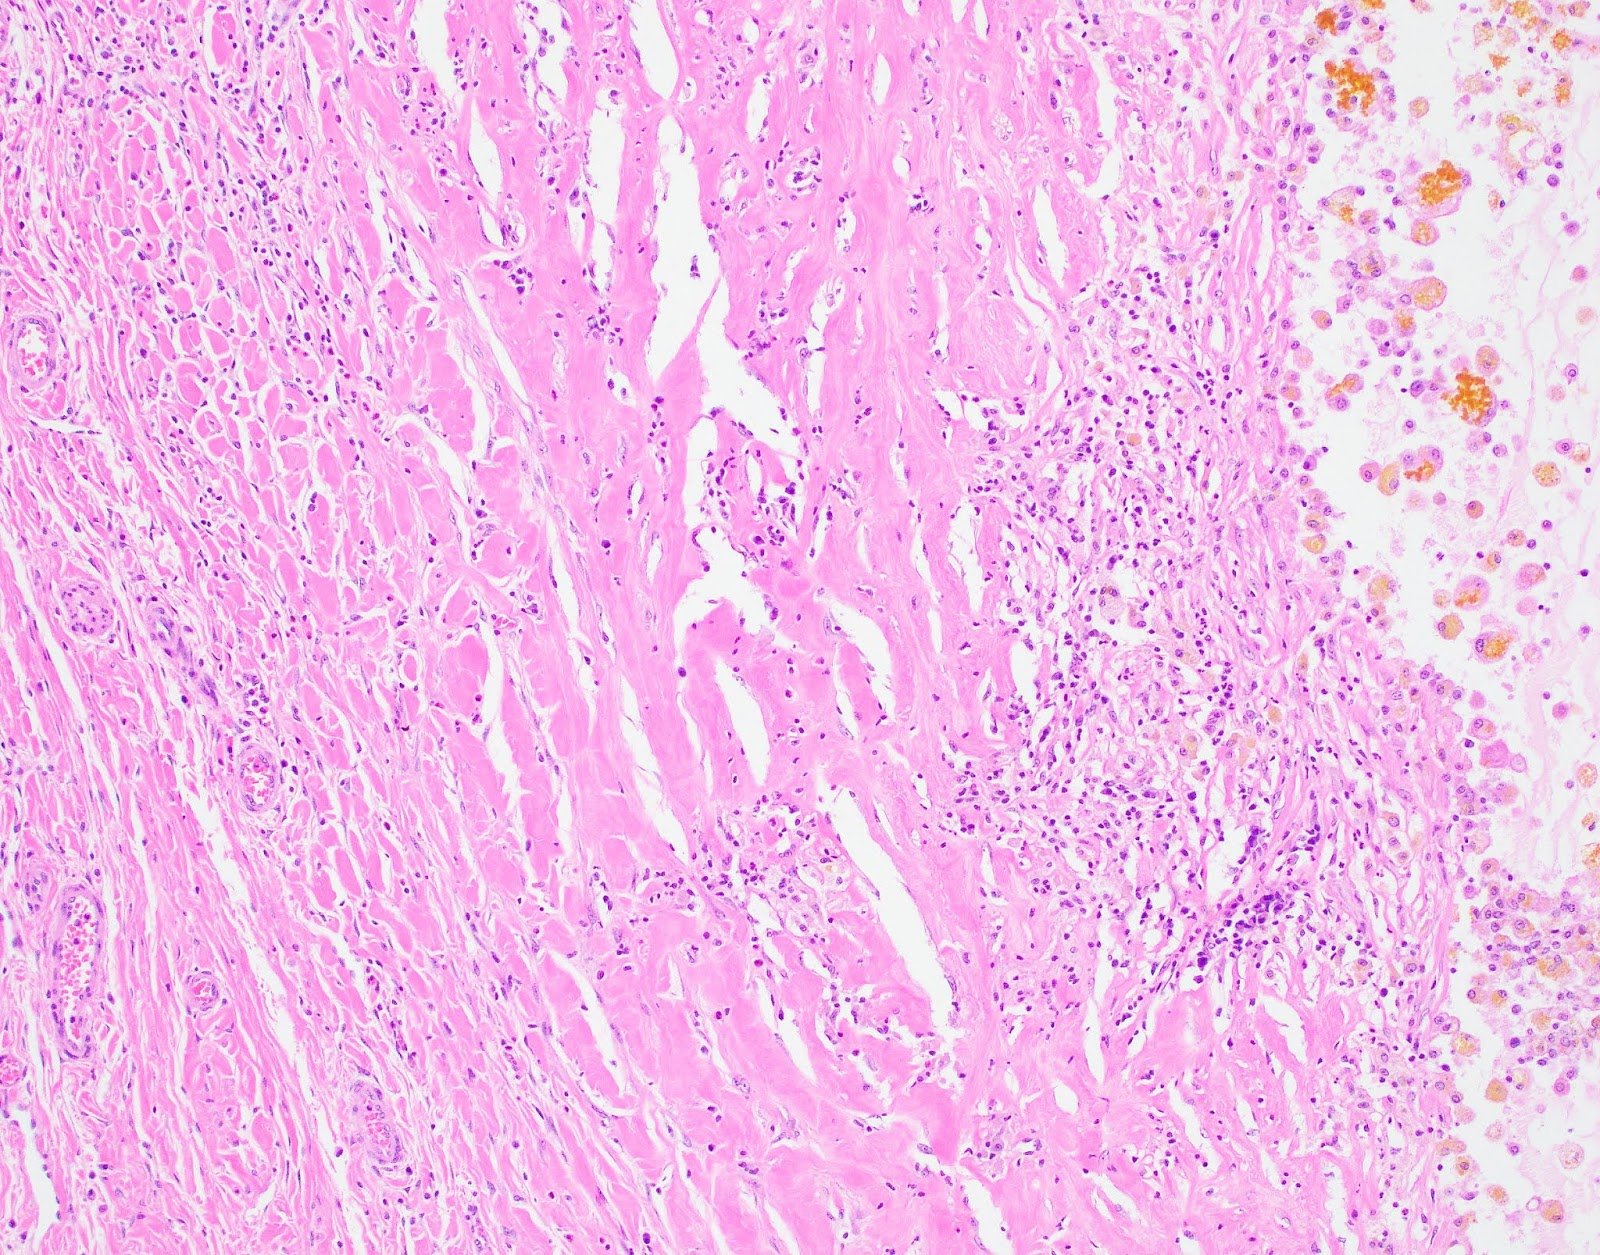

The patient underwent partial liver resection and gross examination showed an 18 x 17 x 5 cm, pink-purple cystic lesion. The cut surfaces were gray-white to pink-yellow with numerous cystic spaces up to 13.5 cm in greatest dimension and cross-sections revealing smaller intramural cysts (Figures 3 and 4). A portion of the specimen was sent for cytogenetic analysis, which failed due to lack of metaphase spreads. Microscopic examination revealed that the lesion was composed of a bland spindle cell population (Figure 5) within a variably loose, edematous, myxoid to hyalinized stroma with scattered ectatic thin-walled vessels, and occasional entrapped large biliary structures, the latter surrounded by dense concentric fibrosis (Figure 6). Grossly appreciated cystic structures were not lined by epithelium, and contained degenerated blood or bile (Figure 7), the latter often with xanthomatous reaction at the periphery (Figure 8). Cords of benign hepatocytes were prominent at the periphery of the lesion (Figure 9).